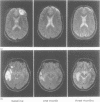

Fifty patients who sustained mild to moderate closed head injury (CHI) underwent a CT scan, MRI, and neurobehavioural testing. At baseline 40 patients had intracranial hyperintensities detected by MRI which predominated in the frontal and temporal regions, whereas 10 patients had lesions detected by CT. Neurobehavioural data obtained during the first admission to hospital disclosed no distinctive pattern in subgroups of patients characterised by lesions confined to the frontal, temporal, or frontotemporal regions, whereas all three groups exhibited pervasive deficits in relation to normal control subjects. The size of extraparenchymal lesion was significantly related to the initial Glasgow Coma Scale score, whereas this relation was not present in parenchymal lesions. One and three month follow up MRI findings showed substantial resolution of lesion while neuropsychological data reflected impressive recovery. The follow up data disclosed a trend from pervasive deficits to more specific impairments which were inconsistently related to the site of brain lesion. These results corroborate and extend previous findings, indicating that intracranial lesions detected by MRI are present in most patients hospitalised after mild to moderate CHI. Individual differences in the relation between site of lesion and the pattern of neuropsychological findings, which persist over one to three months after mild to moderate CHI, remain unexplained.